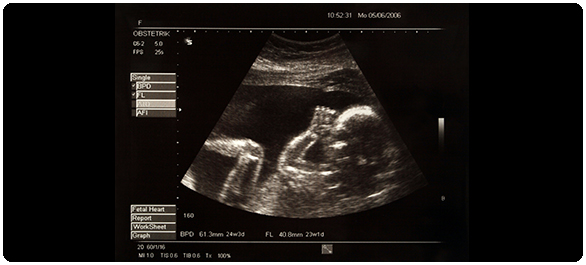

รก(Placenta)เป็นอวัยวะชั่วคราวเฉพาะกิจ มีเฉพาะเพศหญิงในช่วงการตั้งครรภ์ มีหน้าที่หลักในการลำเลียงอาหารและสารชนิดต่างที่สำคัญต่อการดำรงชีวิตของทารกระหว่างมารดาและทารกในครรภ์ ผ่านทางการไหลเวียนเลือด และยังรวมถึงการกำจัดของเสียจากทารก นอกจากนั้น รกยังสร้างฮอร์โมนต่างๆที่เรียกรวมกันว่า “ฮอร์โมนจากรก รกฮอร์โมน(Placental hormones)”เพื่อสนับสนุนภาวะตั้งครรภ์ของมารดาจากการควบคุมการทำงานของ รังไข่ มดลูก เต้านม และเพื่อสนับสนุนการเจริญเติบโตของทารกในครรภ์ ทั้งนี้รกเจริญเติบโตได้จากระบบการทำงานทั้งของมารดาและของทารกในครรภ์ผ่านทางระบบไหลเวียนเลือดของทั้งมารดาและของทารกฯ